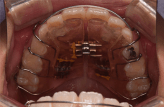

混合歯列期に小学生から始めるマウスピース型カスタムメイド矯正歯科装置(製品名インビザライン完成物薬機法対象外)による治療を開始するためには、次のような適応条件があります。

1. 第一大臼歯が萌出している

2. 切歯のうち少なくとも2歯が2/3以上萌出している

3. 少なくとも3/4顎に乳歯(C、D、E)または未萌出の永久歯(3、4、5)が2歯以上ある

分かりやすくお伝えすると、小学校低学年の年齢が概ねこの時期に該当します。

これらを満たす場合に治療を始めることができ、早期に歯並びや骨格へアプローチを開始することができるのです。